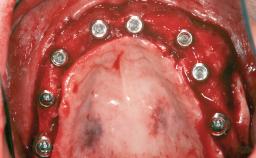

# of Teeth 6

# of Implants 4

Type of Implants One-Piece|Reduced-Diameter

Attachment One-Piece|Reduced-Diameter